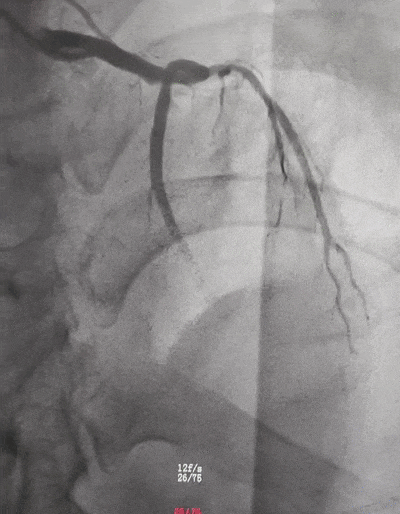

心血管内科各种常见病、多发病、疑难病的诊治,尤其擅长心内科急危重症的抢救及各种心血管疾病的介入诊治,例如冠心病、急性心肌梗死的介入诊疗以及高血压病、心律失常、急慢性心力衰竭、心脏瓣膜病、心肌病、结构性心脏病等的诊治。参与宝安区最早期的心血管疾病介入诊治及急性心肌梗死救治体系建设,介入诊治手术量超过8000例。